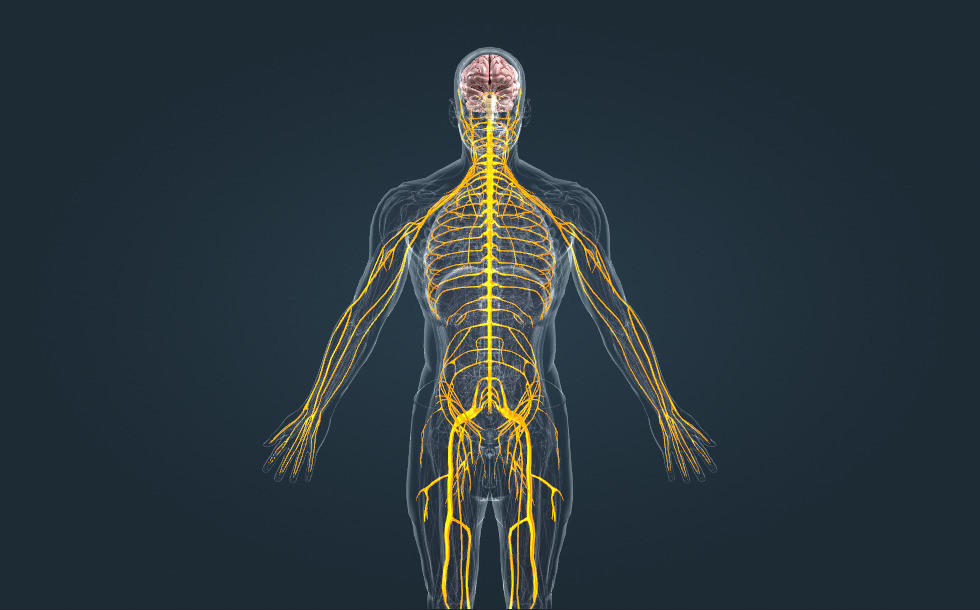

Sistema nervioso

- cerebro - Se sitúa en el cráneo.

- médula espinal - Se sitúa en la columna vertebral.

- nervios - Consiste en las fibras nerviosas que conectan el sistema nervioso central con varios órganos.

El sistema nervioso, junto con el sistema hormonal, se encarga del funcionamiento coordinado y regulado del cuerpo. El sistema nervioso central consiste en el cerebro y la médula espinal, mientras que el sistema nervioso periférico consiste en los nervios, que transmiten la información entre el sistema nervioso central y los órganos mediante señales eléctricas. Hay 12 pares de nervios craneales que se originan directamente en el cerebro, y 31 pares de nervios espinales que se originan en segmentos de la médula espinal.

El sistema nervioso, junto con el sistema hormonal, se encarga del funcionamiento coordinado y regulado del cuerpo. El sistema nervioso central consiste en el cerebro y la médula espinal, mientras que el sistema nervioso periférico consiste en los nervios, que transmiten la información entre el sistema nervioso central y los órganos mediante señales eléctricas. Hay 12 pares de nervios craneales que se originan directamente en el cerebro, y 31 pares de nervios espinales que se originan en segmentos de la médula espinal.